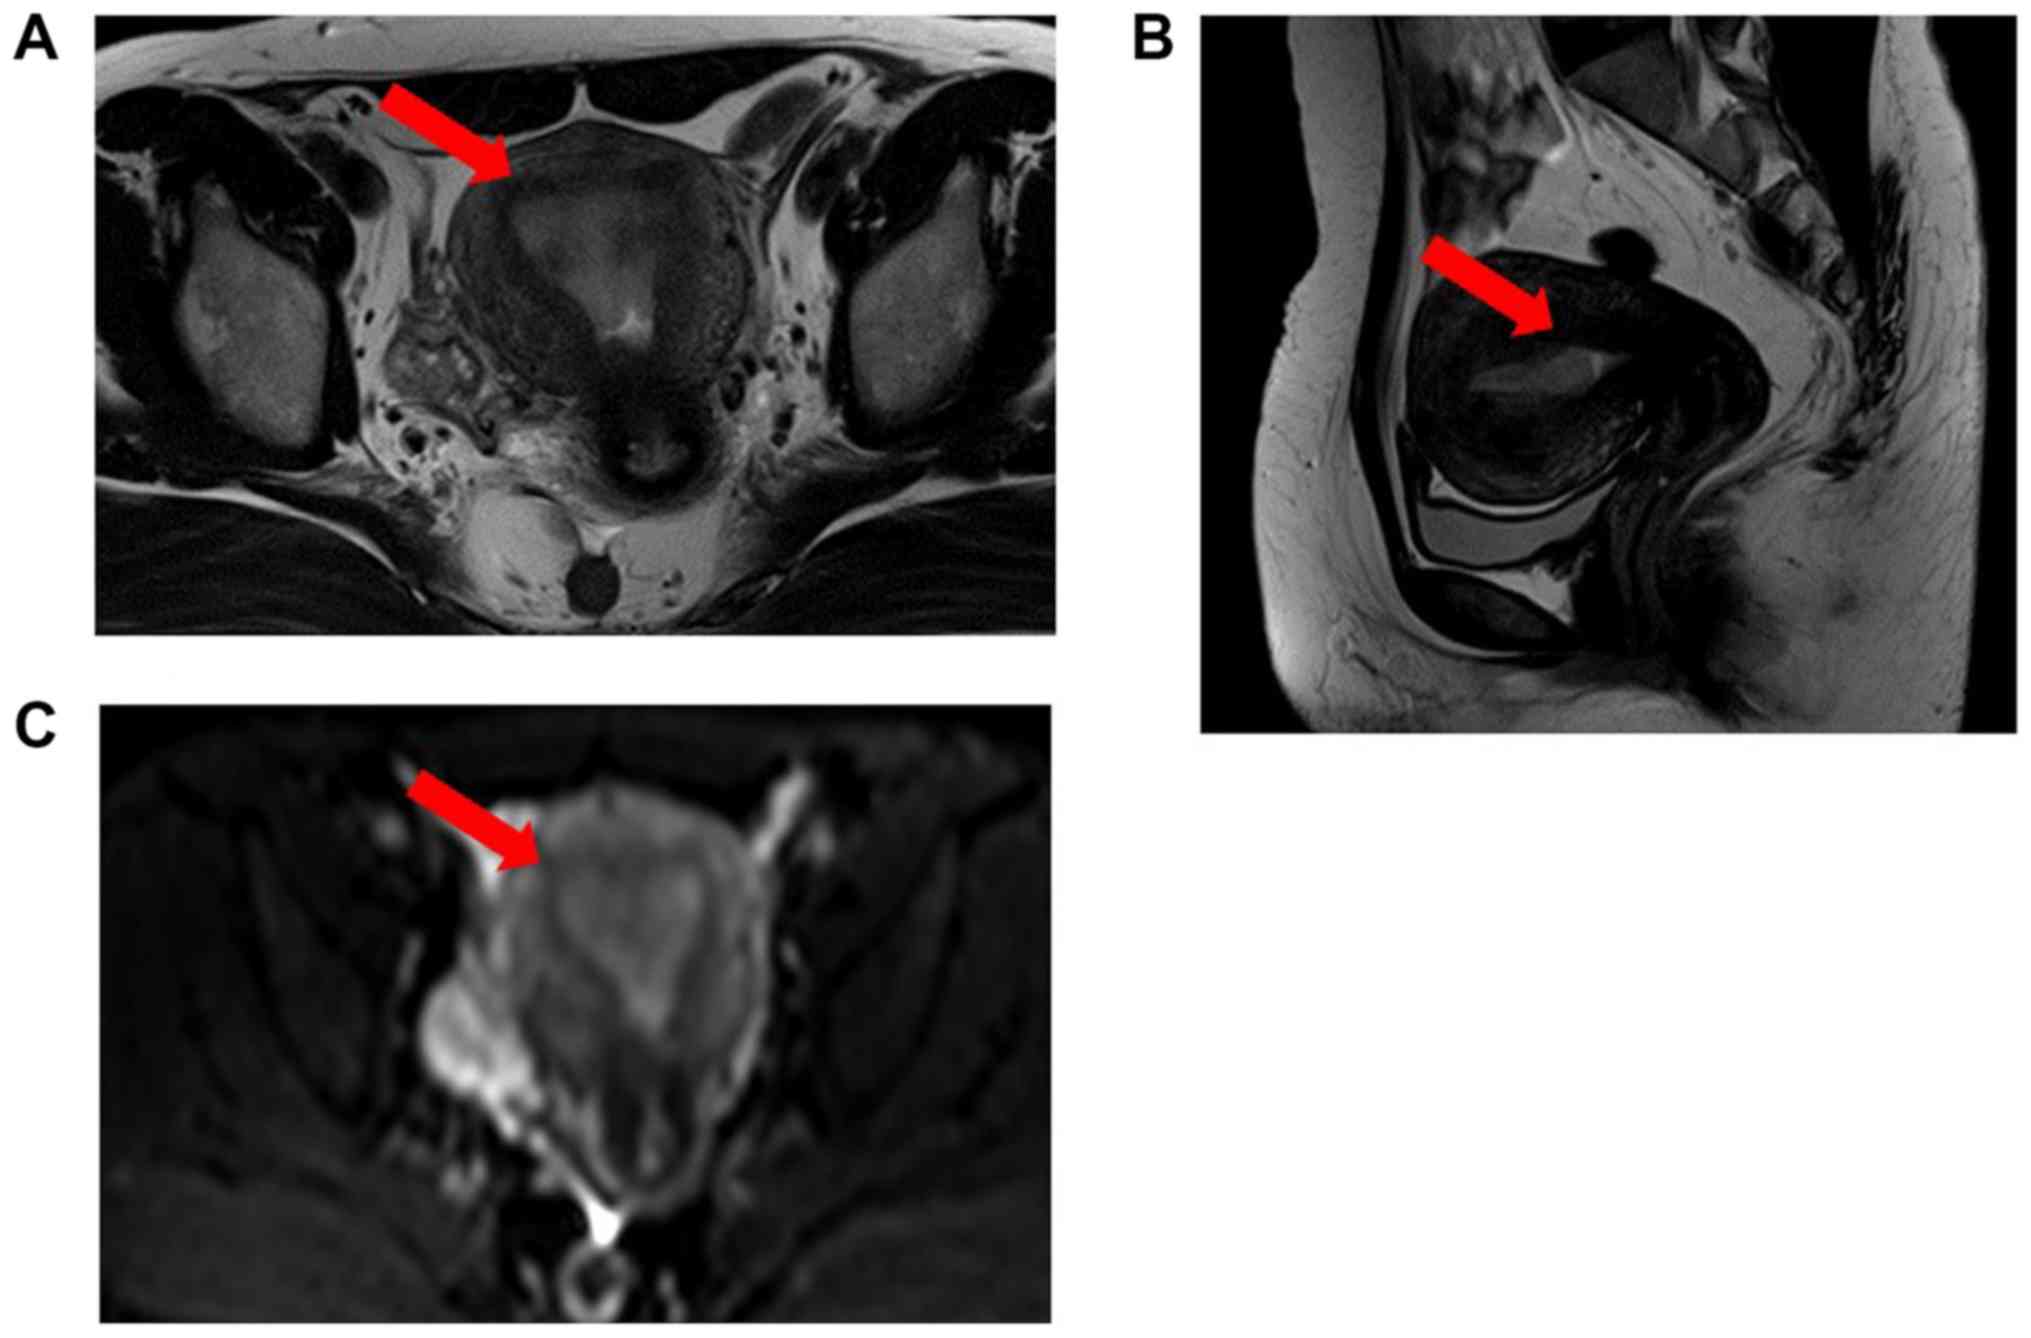

Figure 2

MRI findings. (A) Axial T2-weighted image (T2W1), (B) Sagittal T2-weighted image (T2W1). Although (C) Diffusion weighted imaging MRI showed endometrial thickness (red arrows) and endometrial cancer was not suspected. MRI, magnetic resonance imaging.